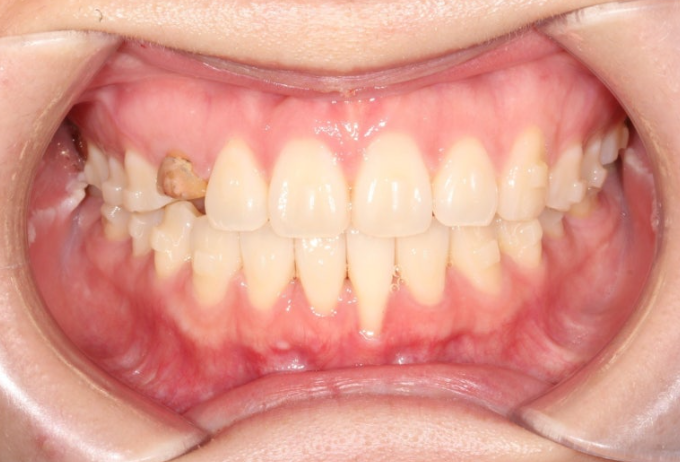

24년 11월, 1번 장치를 끼기 시작했습니다. 25년 3월까지 14개 장치를 모두 낀 후 모습입니다.

25.03

기울어져있던 앞니 치축은 똑바로 개선되었으며 블랙트라이앵글 사이즈는 많이 줄었습니다. 중심선은 아직 개선이 필요합니다.